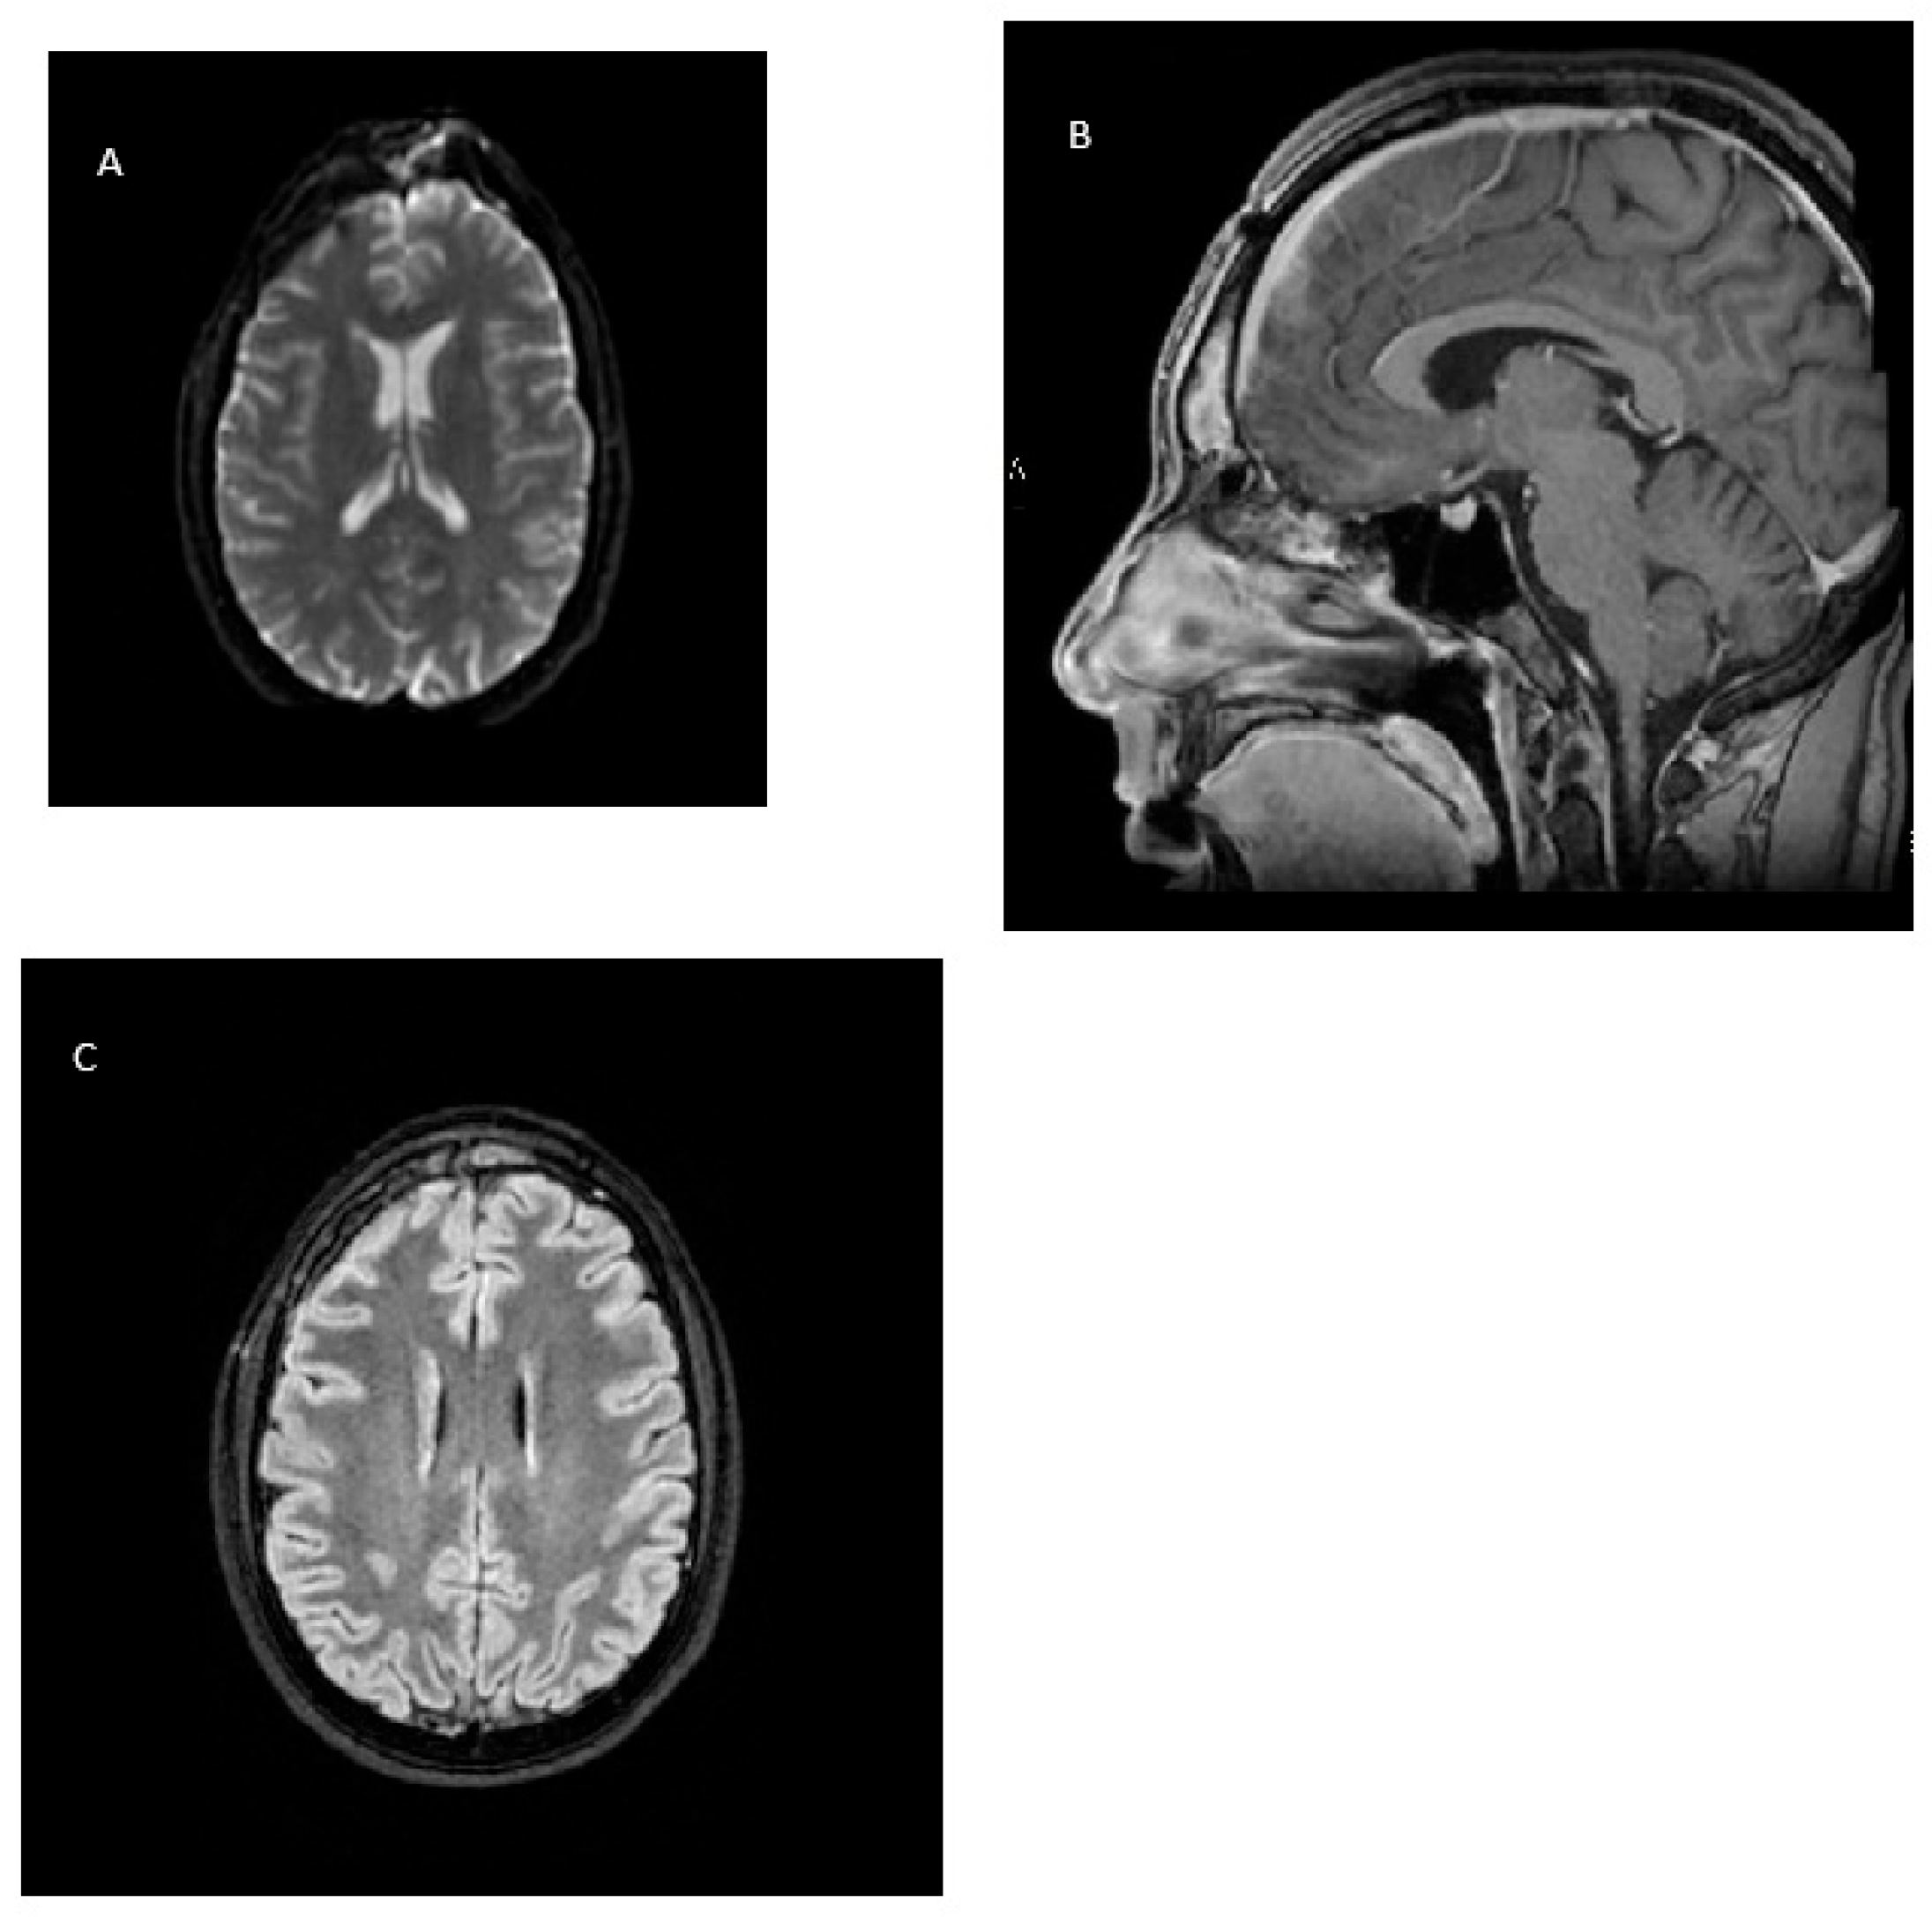

2. Case Report